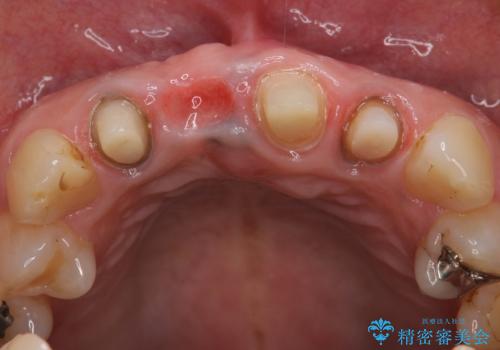

- 右上の前歯が折れてしまったので診て欲しいといらっしゃった方の症例です。

右上1番目の歯は保存不可能だったため抜歯し、ブリッジによる補綴を行いました。